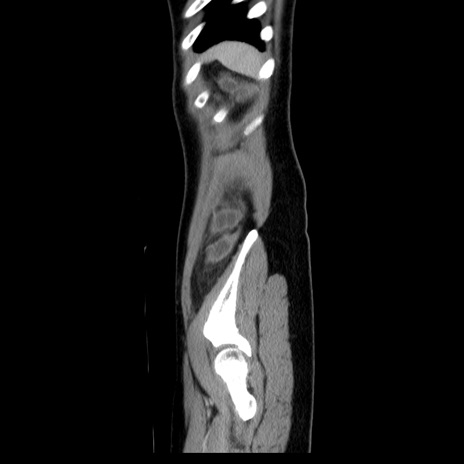

症例39(矢状断像)

CT